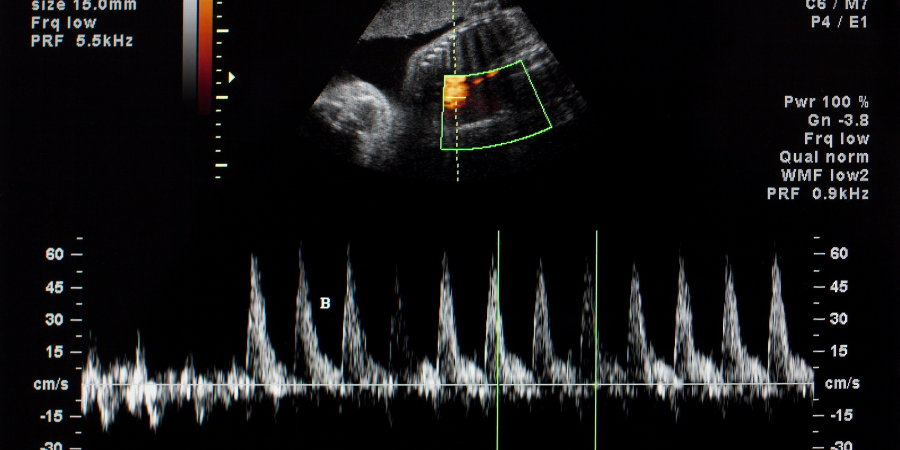

USG dopplerowskie

Służy do oceny przepływu krwi w naczyniach krwionośnych i sercu. Wykorzystuje się tu fakt zmiany długości fali odbitej od przedmiotu, który zbliża się lub oddala od głowicy. W przypadku USG takim przedmiotem są krwinki czerwone. Analizując odbitą od nich falę ultradźwiękową, można wykreślić kierunek i sposób przepływu krwi. Mierząc obszar zmiany barwy, jego kolor i nasycenie, dowiadujemy się np., że: jest nieszczelna zastawka mitralna w sercu; w aorcie znajduje się skrzeplina, która zaburza przepływ krwi, przewód Bottala jest drożny.